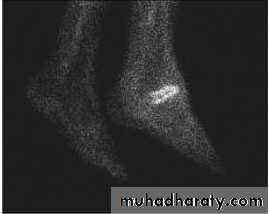

Bone scans, such as the white blood cell labeled Indium-111, Technetium-99m HMPAO and Sulfur Colloid Marrow Scan,

distinguishing acute and chronic infections,

identifying OM from Charcot neuroarthropathy